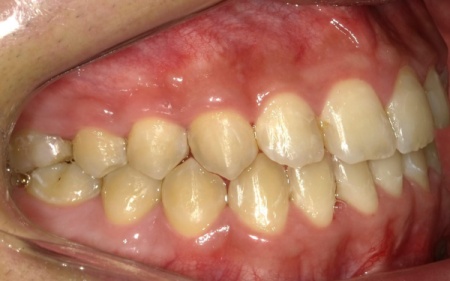

10代男性 顎変形症が原因で下顎がずれて非対称になっていた噛み合わせをサージェリーファースト法を併用した矯正治療で改善した症例

拝見したところ、骨格の問題により下前歯が上前歯より前に出ている前歯部反対咬合と、前歯が開いて噛み合わないオープンバイトが認められました。

さらに、下顎の骨が右方向にずれて上下の歯が噛み合う面が斜めになっていることで、顔面の非対称も見られます。

まずは、歯を正しい位置に動かすスペースを確保するために、左下奥歯(第1小臼歯)を抜きました。続いて、サージェリーファースト法による下顎骨骨切り手術を慎重に行います。

次に、上下の歯にマルチブラケット装置を装着し、歯を動かす起点とするためにアンカースクリューを埋入します。

今回は患者様と相談のうえ、治療中の審美性を考慮して目立ちにくい色調のブラケットを採用しました。

その後は定期的に来院いただき、ワイヤーの調整を行いながら歯並びと噛み合わせを徐々に整えていきました。